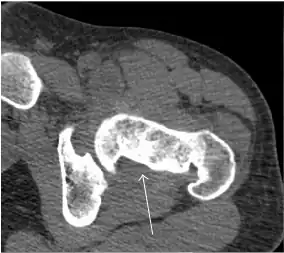

Computed Tomography

Due to radiation concerns, CT has been relegated after MRI in the study of intra-articular causes of hip pain. The only exception where CT is considered superior to MRI is in bone tumors, because of its ability in characterizing matrix calcifications, and in depicting the anatomy of acute traumatic fractures. Typical matrix calcifications include the following: (a) osteoid mineralization, like a dense cloud, (b) chondroid calcification, reproducing a punctate popcorn pattern, or (c) fibrous calcification, ground glass-like appearance. There are also tumors that typically do not show matrix calcification. CT is also used for accurate localization of the nidus in osteoid osteomas and this must be differentiated from Brodie’s abscess or a stress fracture. The current standard treatment of osteoid osteoma is percutaneous radiofrequency ablation and this is usually performed under CT guidance.[1]